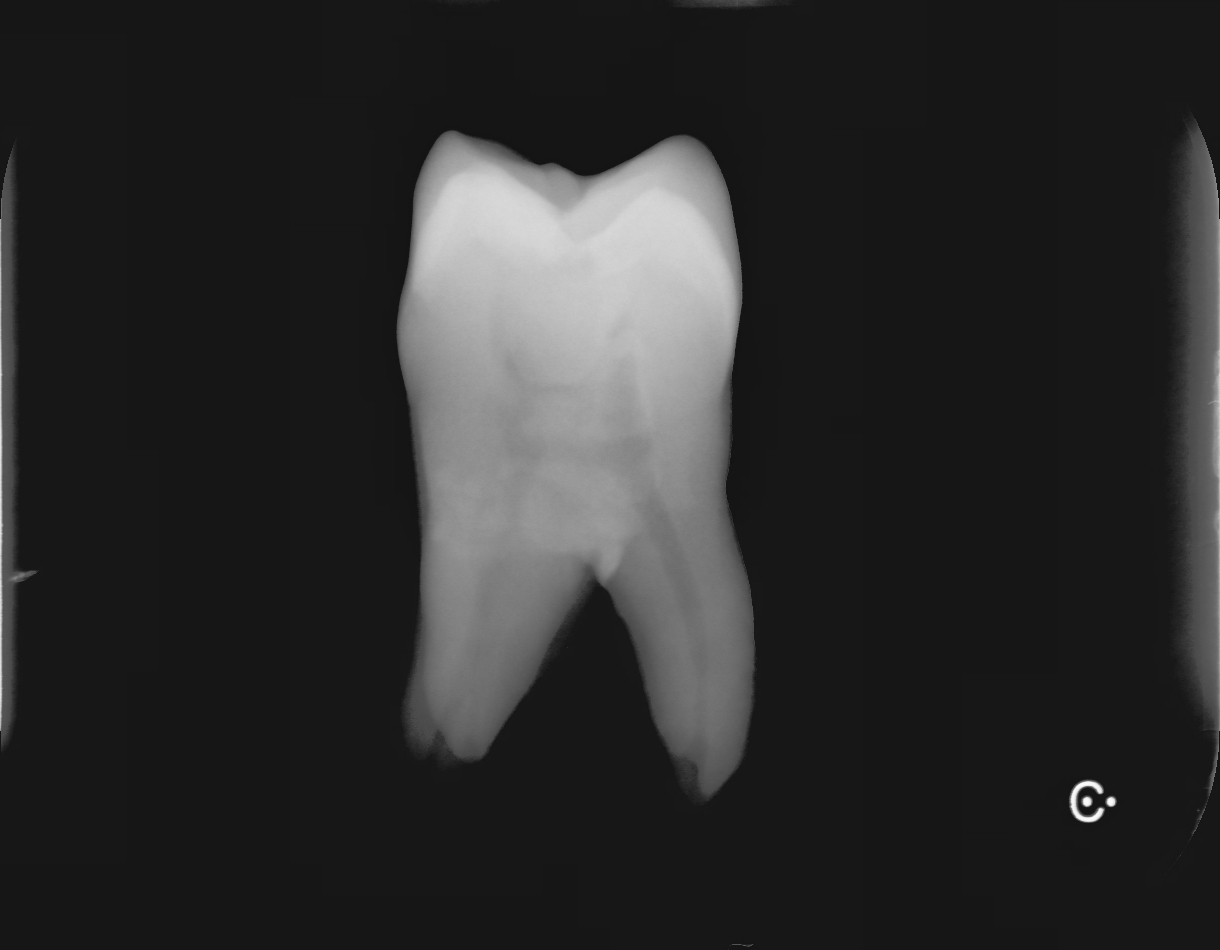

根が完成するまでに歯が生えてから2~3年。そろそろかとレントゲンを撮って見てみると、昨年のレントゲンで開いていた根の先が今年のレントゲンでは閉じてきています(緑〇)今年のレントゲンで一番前の永久歯はほぼ完成したようです(赤〇)

昨年のレントゲン

今年のレントゲン